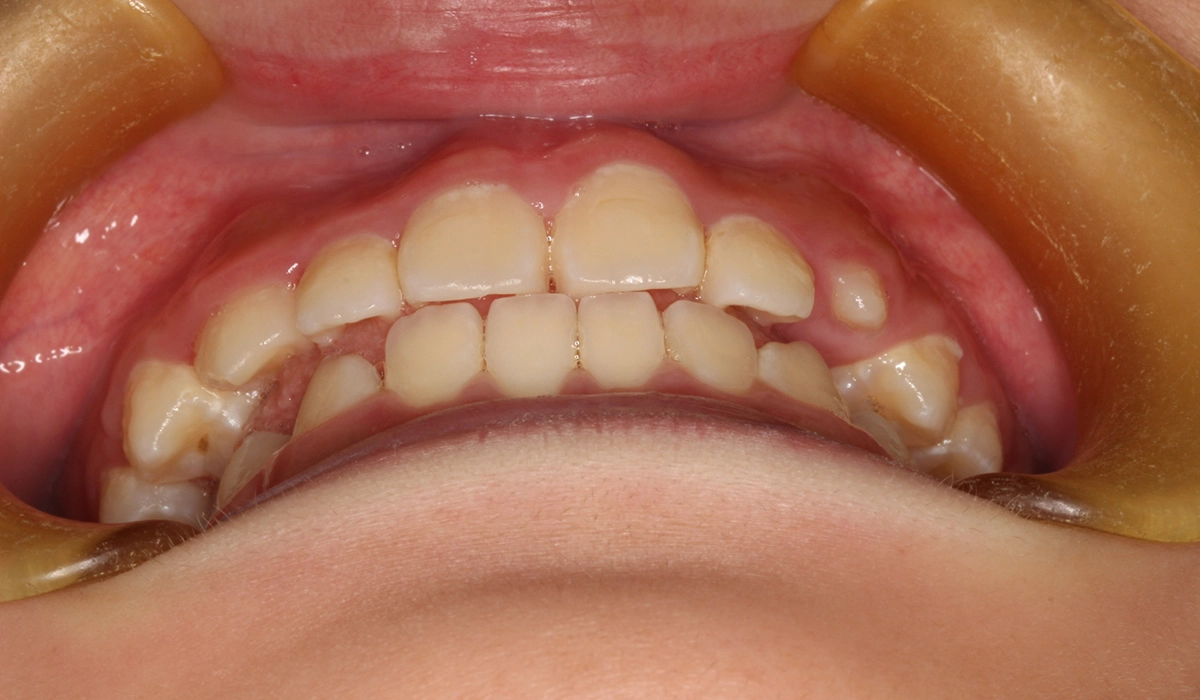

今回ご紹介する患者様は、前歯の捻れを気にされており、矯正検査後叢生Ⅰ級と診断いたしました。

主訴 前歯の捻れが気になる

治療内容 前歯の捻れを気にされており、矯正検査後叢生Ⅰ級と診断いたしました。